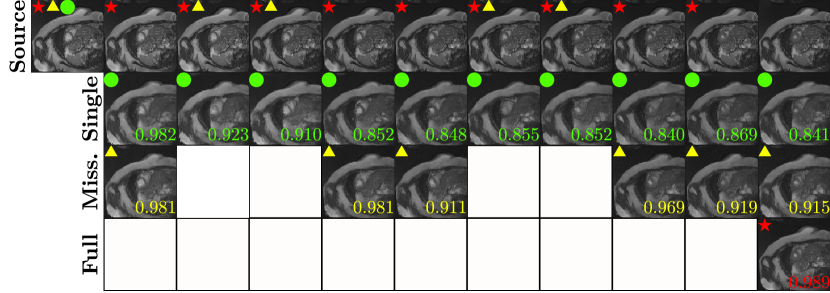

Refer to caption

Figure 5: An illustration of different settings for input sequence. The first row shows the ground-truth progression from ED frame to ES frame. The symbols in upper left corner of images in the first row is the conditioning image 𝐗𝒞superscript𝐗𝒞\mathbf{X}^{\mathcal{C}} (red star for full sequence, yellow triangle for missing data, and green circle for single image). The remaining rows show the synthesized images with single image, missing data, and full sequence settings, respectively. The numbers on bottom right corner of each image is the SSIM between the ground truth and the synthesized frame.

In this section, we perform an ablation study on the components of our model with various settings for the input sequences. First, we experiment with different settings for the input sequence defined in the first paragraph of Section 4.1, i.e., single image, missing data, and full sequence settings. As presented in Fig. 5, synthesis using the full sequence and missing data settings show a higher SSIM compared to a single input setting. Also, as observed by the high peak in SSIM for frames in the vicinity of conditioning frames, our SADM is learning which frames of the input sequence are important in generating future frames, i.e., the sequential dependency. Next, we perform an ablation study by removing either the attention module or the diffusion model.